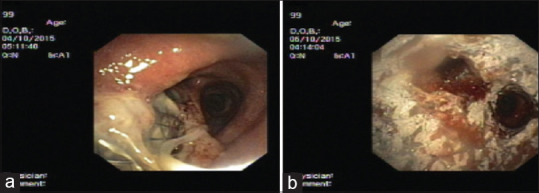

Case series of Y shaped self-expanding metallic stents (Y-SEMS) for central airway obstruction - Experience of deployment with 'Single Guide Wire' technique.

Y形自膨胀金属支架(Y- sems)治疗中央气道阻塞的病例系列-“单导丝”技术部署的经验。